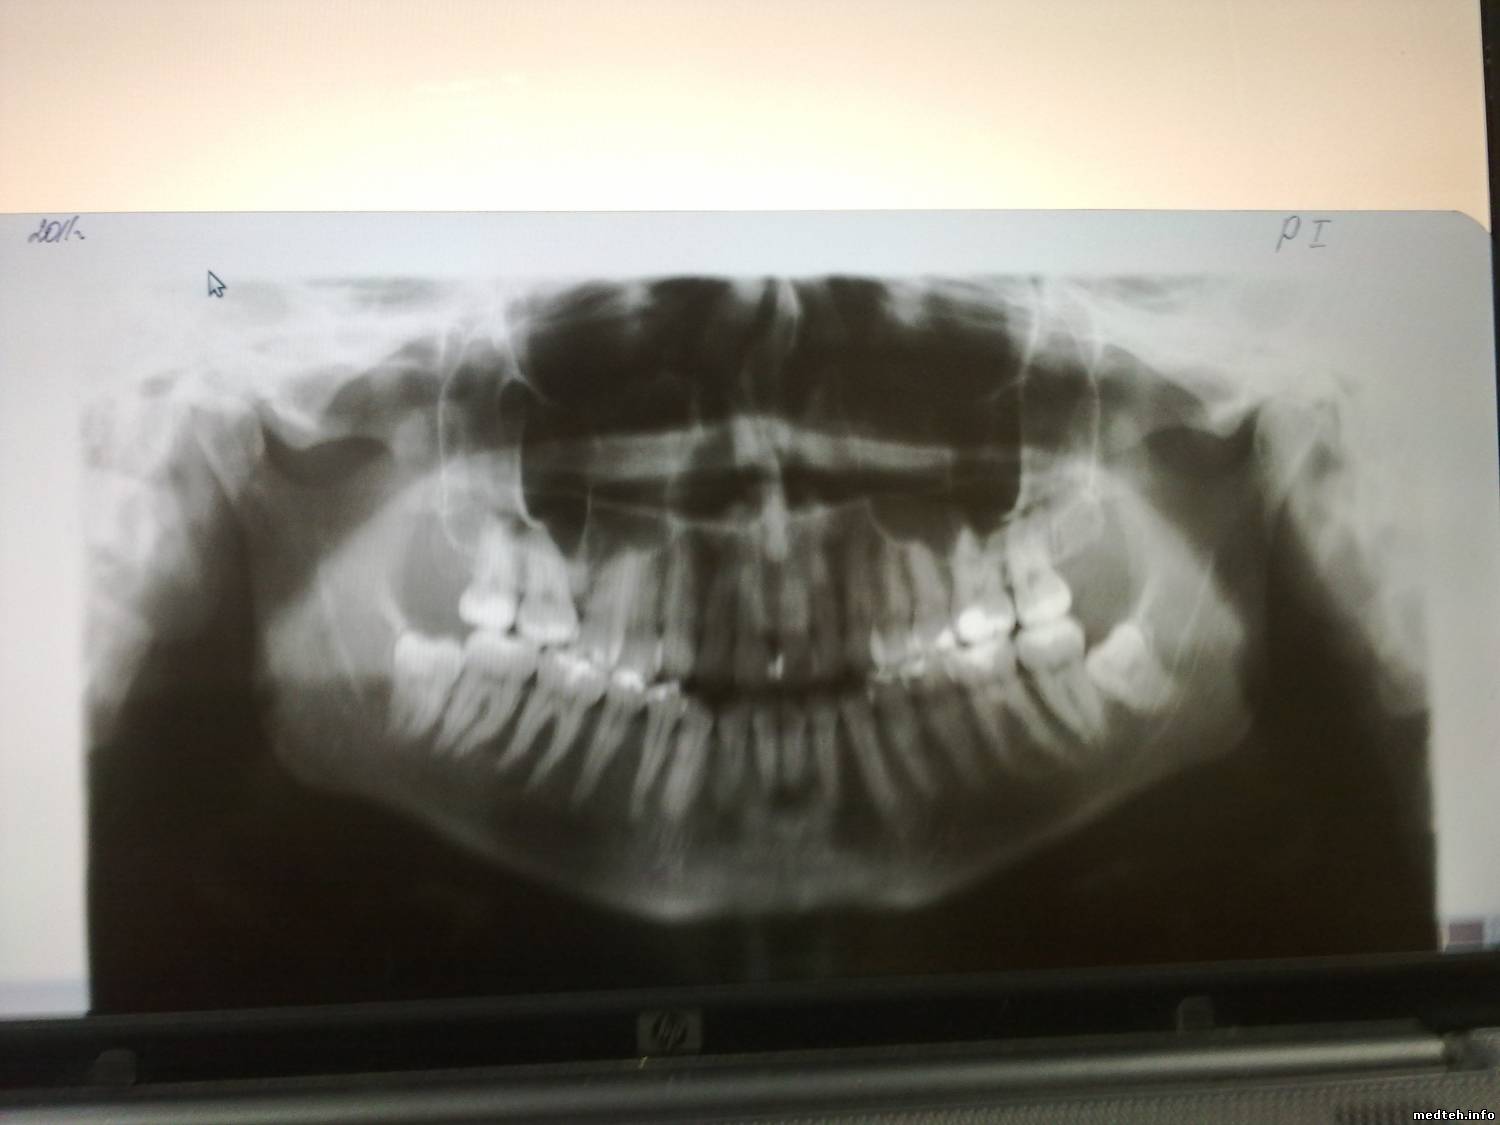

Периодически на снимке появляется следующая полоса: как буд-то засвет. В чем может быть причина?

9915510.jpg (84.7 Kb)

неправильное позицирование , голова сильно выставлена вперёд .

неправильное позицирование , голова сильно выставлена вперёд

проверить кассету- на экране вмятина или сильный залом. возможно, что пленку при установке в кассету повредили.

Скорее всего проблема в калибровке рентгена. Необходимо установить фильтр на рентгеновскую трубку. Если штатного нет подойдет стальная пластина толщиной 2-2.5мм. После этого заходим в режим калибровки и добиваемся горизонтальной калибровочной кривой.Режим 60 Кв экспозиция 11 сек. Калибровочная кривая должна быть горизонтальной без отрицательных импульсов. Если дело в калибровке то все исправится.

Цитата Толя ()

Скорее всего проблема в калибровке рентгена.

неа, см . картинку синяя линия- граница снимка(поля засветки пленки). часть дефекта выше этой линии. так что с диафрагмой не связано.

2715208.jpg (140.7 Kb)